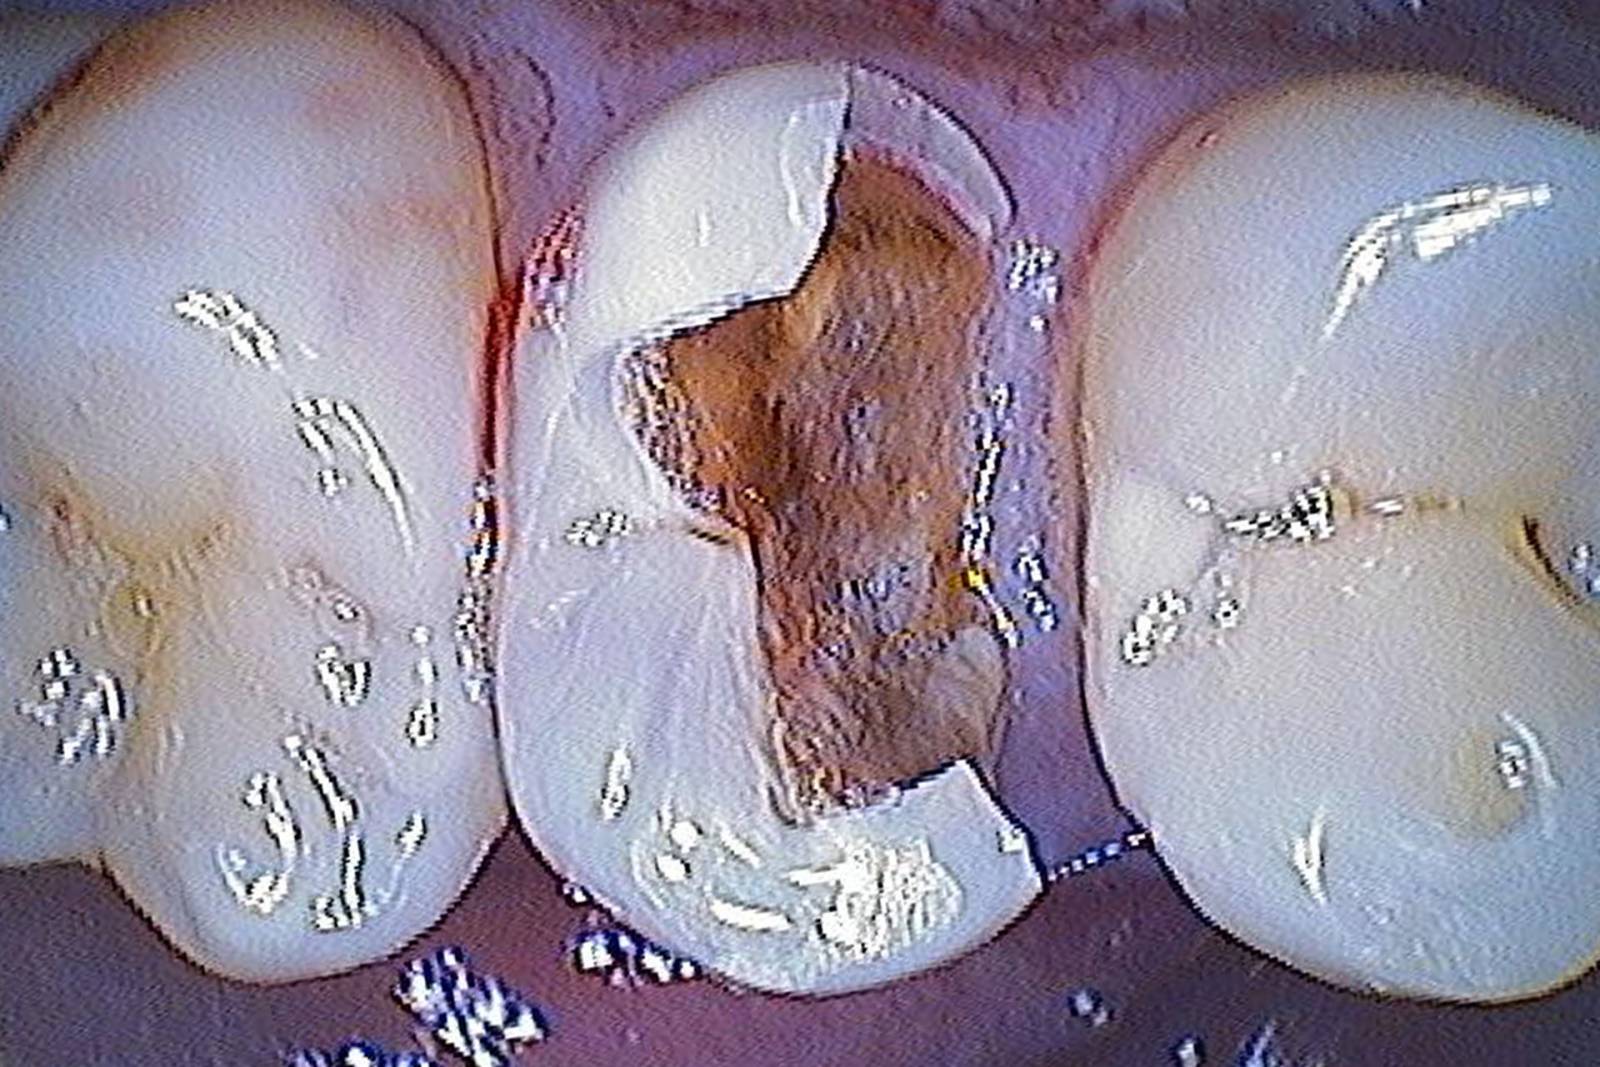

Before

Insufficient fillings in the second quadrant. The restorations were about 15 years old.

After

Chairside-fabricated crowns made from CEREC Tessera (teeth 26/27). Inlays for teeth 24 and 25 made of composite blocks.